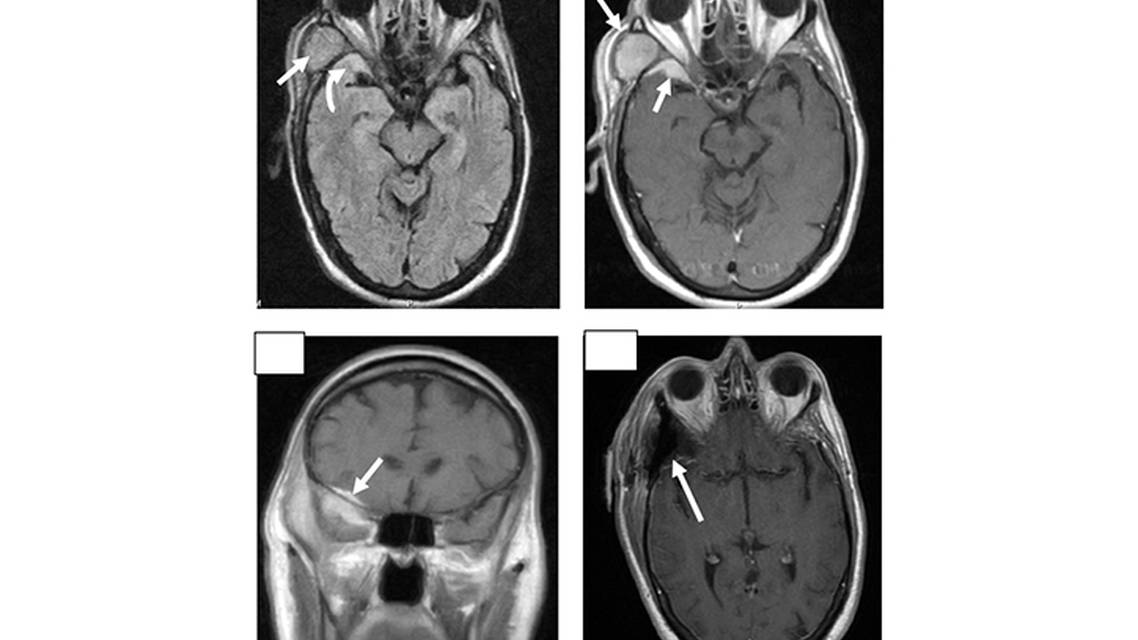

SA underwent both CT head and MRI brain, which demonstrated a dural-based enhancing meningioma compressing the anterior temporal lobe that extended into the lateral orbit with attachments to the optic nerve, as well as intraosseous involvement and extension extracranially into the temporal fossa and along the posterior sphenoid wing (Figure 2). Several weeks after the initial diagnosis, SA underwent a craniotomy with complete resection of the meningioma. During the procedure, pathology was collected from the bone and soft tissue mass in the right extracranial temporal bone, the right frontal temporal dura, and the tumor-infiltrated temporal bone.

Once the palpable mass was identified, an MRI brain and CT head were performed. The MRI demonstrated a dural-based enhancing mass. The mass had intraosseous involvement, extended into the right temporal masticator space, and showed enhancing soft tissue within the right middle cranial fossa, likely secondary to a sphenoid wing meningioma. The CT redemonstrated an enhancing soft tissue mass in the right temporal region measuring approximately 3.5 x 2 cm and extending inferiorly along the right temporalis muscle into the right masticator space. There was a thin band of extra-axial soft tissue enhancement within the right middle cranial fossa, likely secondary to the meningioma. Hyperostotic bone changes were confirmed by the CT (Figure 1).